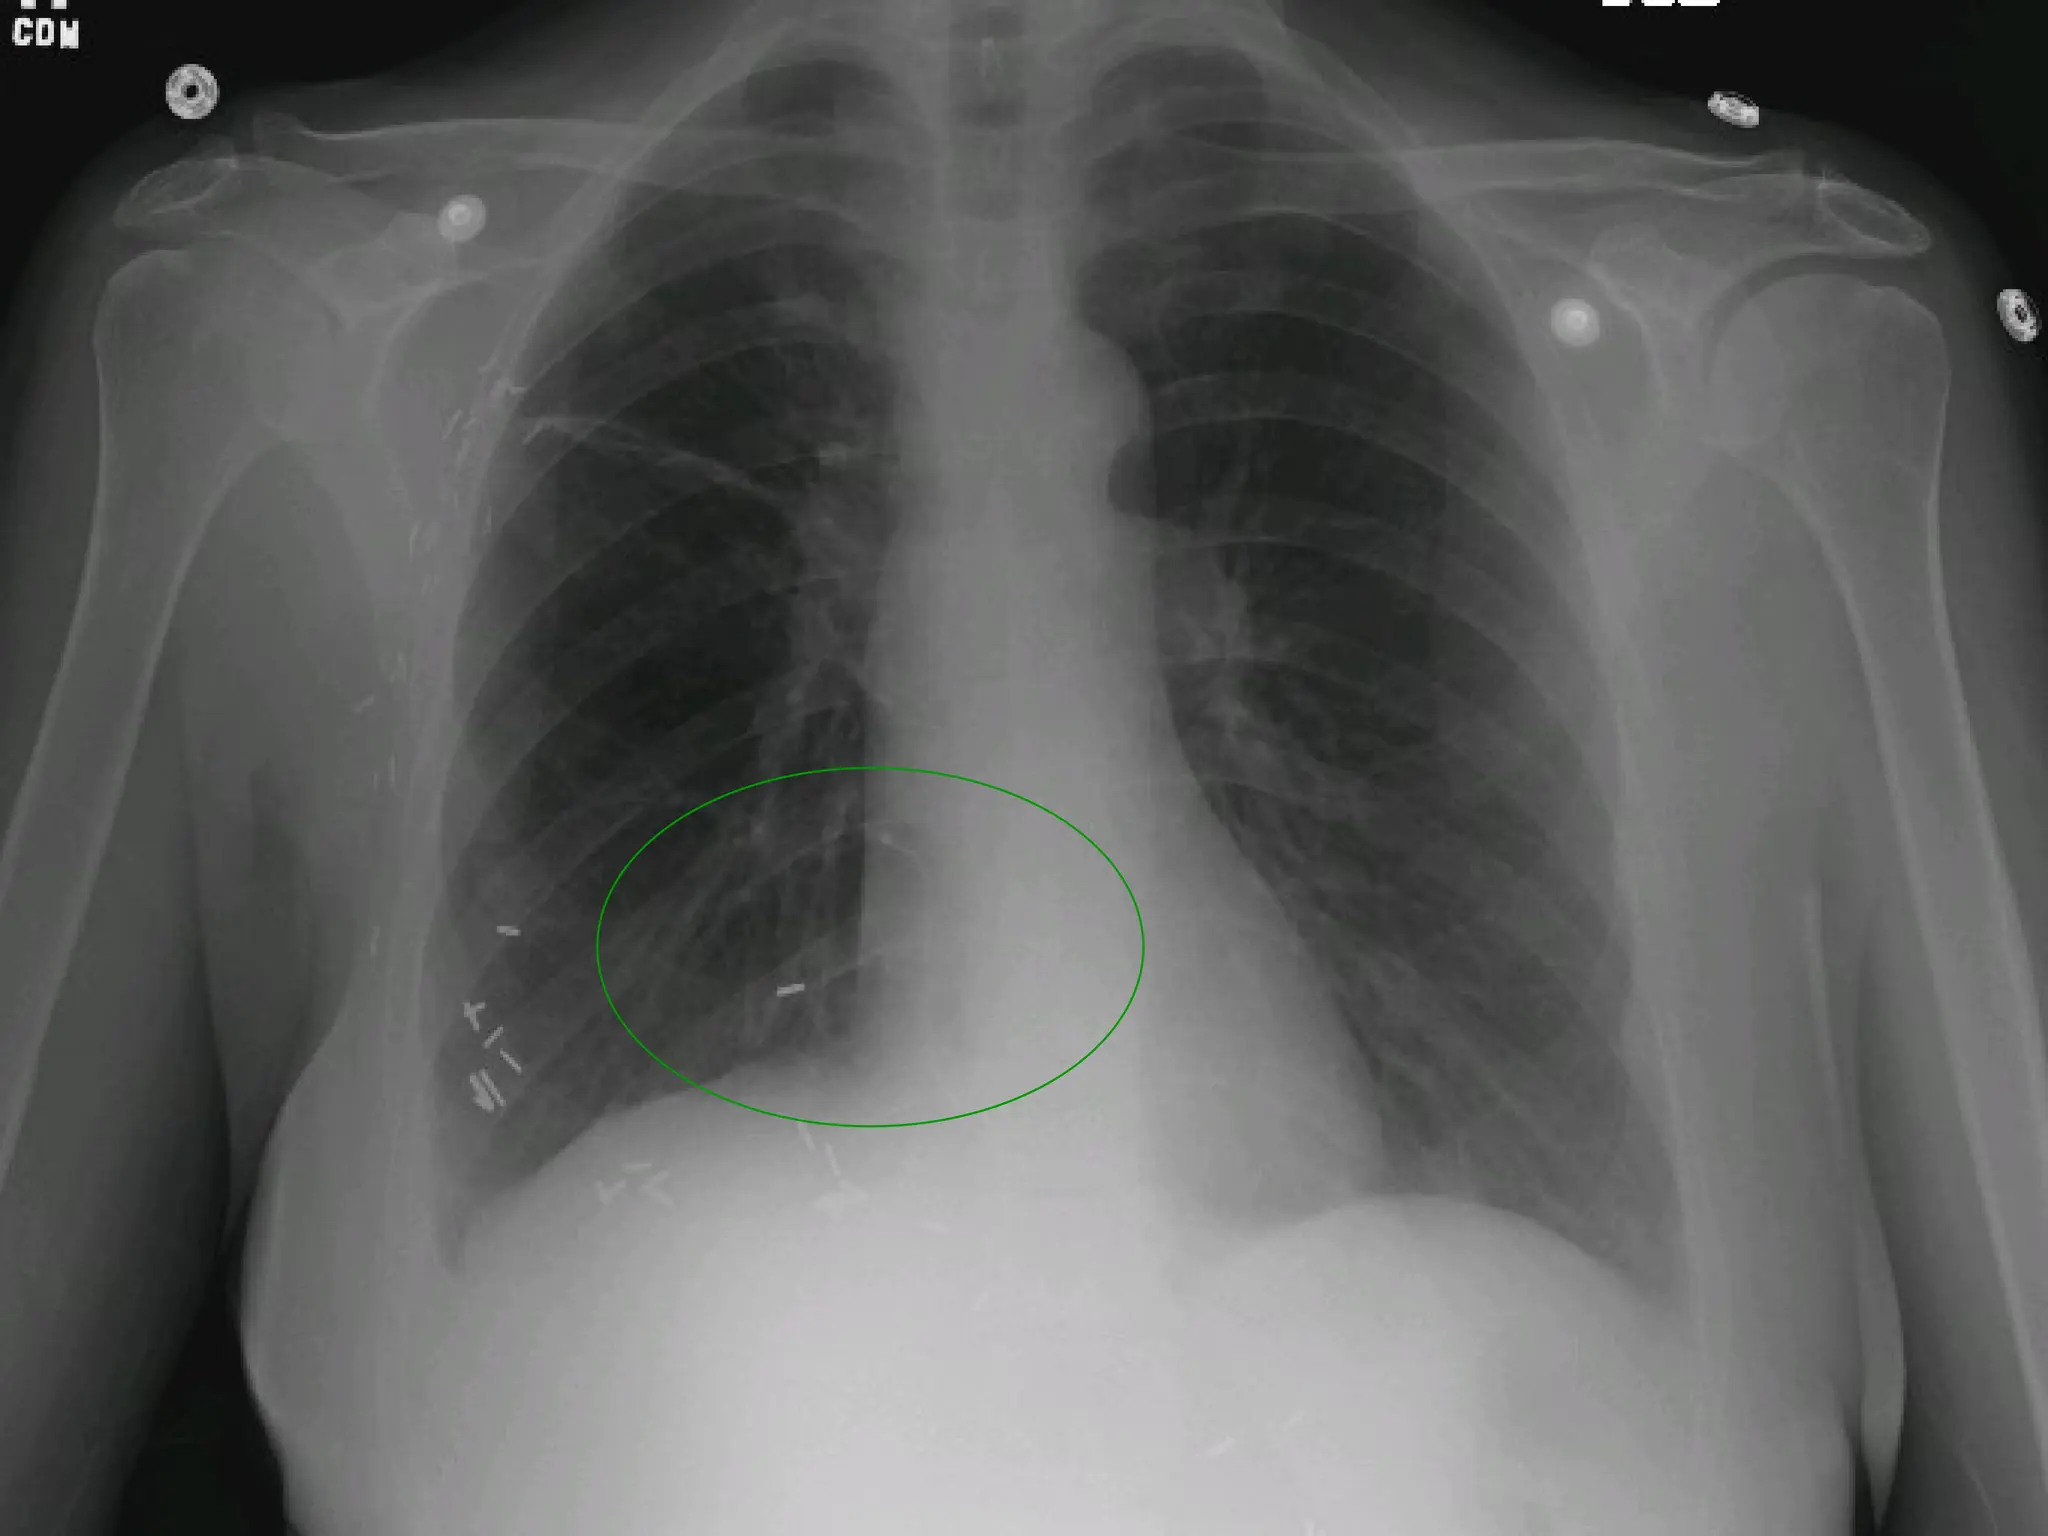

A broken central venous catheter has

migrated into the right lower

lobe pulmonary artery